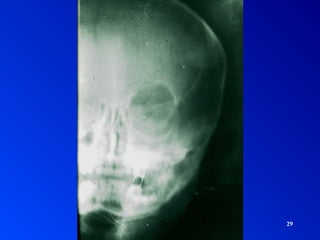

SINUSITIS Interrogatorio SintomatologíaExamen Físico Palpación – percusión Rinoscopia anterior Rinoscopia posterior Exámenes complementarios Imagenología: Rx, TAC, RM Fibroscopía - Endoscopía Punción DIAGNOSTICO

• 29.